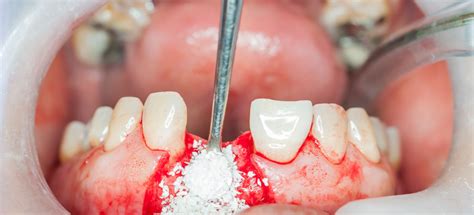

El injerto de hueso dental es un tratamiento de regeneración ósea en el cual se coloca relleno óseo protegido por una membrana. En muchas clínicas, esta técnica se usa para corregir defectos óseos o para ganar altura y anchura en el hueso, lo que permite la colocación exitosa de implantes dentales.

Para asegurar la supervivencia del implante, es fundamental disponer de una cantidad de hueso dental o masa ósea mínima. Cuando la pérdida ósea está avanzada, no se pueden colocar implantes dentales sin antes hacer un injerto de hueso dental. Poner hueso en un implante dental permite que este tenga el soporte adecuado para su éxito y osteointegración.

La función del injerto de hueso para implante dental es aumentar la zona carente de hueso y aumentar la cantidad ósea en la zona donde se quiere colocar el diente fijo.

- Injerto de hueso (si es necesario): Si falta hueso, recomendamos un injerto de hueso. Coste: En España, un pequeño injerto con material sintético puede costar alrededor de 200€-400€.